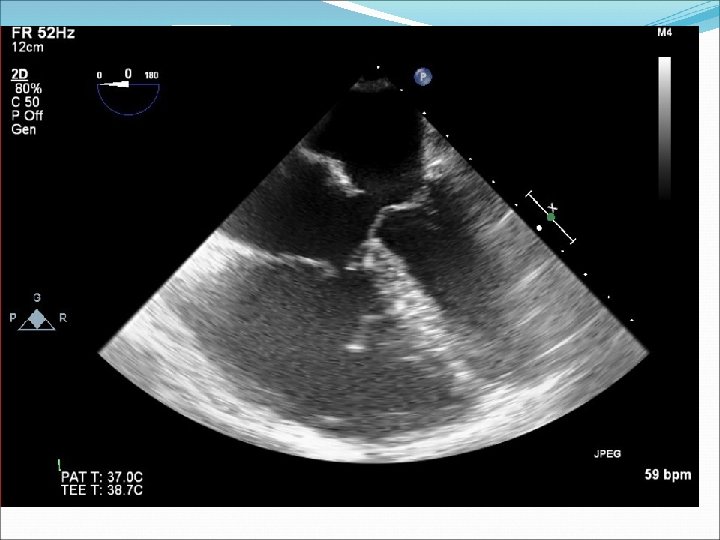

Ebsteinova anomálie �Vzácná vrozená vada � Abnormálně vyvinutá trikuspidální chlopeň je posunutá apikálně do pravé komory, septální a zadní cíp chlopně v různém rozsahu adheruje k endokardu pravé komory. K uzavírání chlopně tedy dochází hlouběji v pravé komoře, je obvyklá trikuspidální regurgitace. Vada bývá různě vyjádřená, od nevelkého posunu zóny koaptace cípů do dutiny pravé komory až po nálezy obrovské pravé síně, kterou tvoří i část původní, nyní atrializované pravé komory, samotná pravá komora je jen velmi malá. �Vada bývá spojena často s defektem septa síní nebo perzistujícím foramen ovale patens. Původně je přítomen levopravý zkrat, který se při těžké trikuspidální regurgitaci a selhávání pravé komory obrací na pravolevý. Pro vadu je typická přítomnost akcesorních atrioventrikulárních spojek převodního systému. Při vzniku supraventrikulární arytmie se těmito spojkami impulzy převádějí ze síně na komory a dochází ke vzniku maligní komorové arytmie.